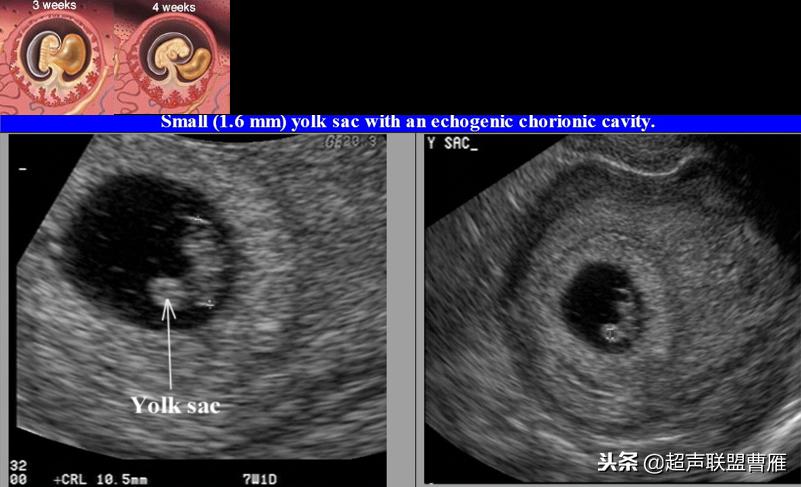

小卵黄囊,预后不良

· 卵黄囊过小:有可能自然流产或难免流产(与流产有关)

· 卵黄囊不规则或钙化:出现囊壁钙化或者增厚等形态改变以及囊壁缺损,提示 卵黄囊功能衰退与营养障碍,预示妊娠结局不良。一般情况下,出现钙化通常胚胎已停育。

卵黄囊过小2mm